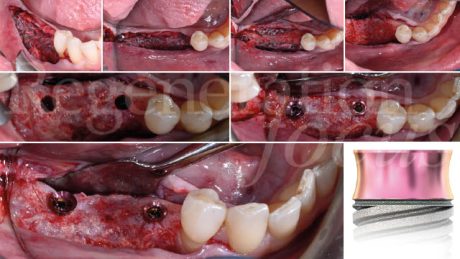

L’intervento chirurgico è stato eseguito in anestesia loco-regionale. È stato elevato un lembo trapezoidale composto da un’incisione crestale e da un’incisione verticale di svincolo posizionata due elementi mesialmente al difetto, mentre distalmente l’incisione è proseguita nella regione retromolare (Fig. 4). Particolare attenzione è stata posta al rilascio periostale, eseguito sia vestibolarmente che lingualmente, permettendo una mobilizzazione coronale di entrambi i lembi di circa 8 mm senza tensione.

La mesh customizzata si è adattata perfettamente al sito ricevente, confermando la precisione della pianificazione digitale (Fig. 5). Il materiale da innesto è stato preparato combinando osso autologo particolato, raccolto dalla linea obliqua esterna mediante grattino monouso (SafeScraper, Meta), con osso bovino deproteinizzato di granulometria 0,25-1 mm (Geistlich Bio-Oss®) in rapporto 50:50. A questa miscela sono stati aggiunti 0.3 ml di gel a base di polinucleotidi e acido ialuronico (Regenfast®), creando una mixture bioregenerativa che è stata accuratamente compattata all’interno della mesh (Fig. 6).

La fissazione è stata ottenuta mediante tre viti in titanio da 1.5×5 mm (Viti FYxoss, MCbio) posizionate strategicamente (Fig. 7). Una membrana in collagene 30×40 mm (Geistlich Bio-Gide®) è stata posizionata a copertura della mesh (Fig. 8). La chiusura primaria tension-free è stata ottenuta con suture orizzontali a materassaio e punti staccati (Fig. 9).